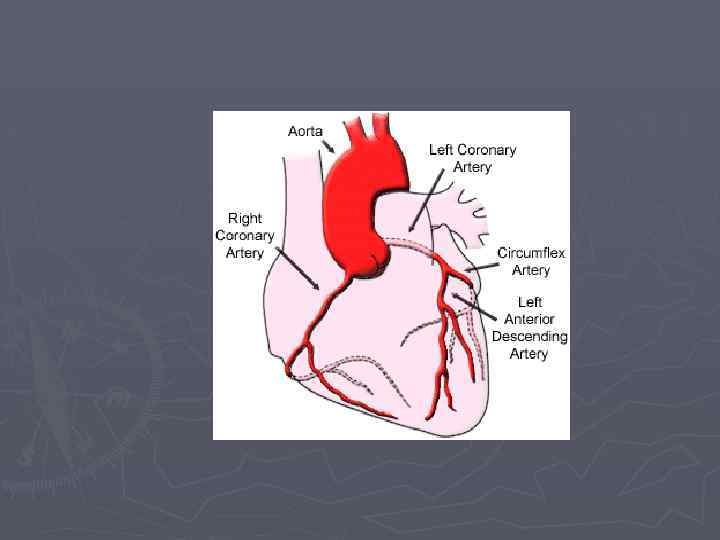

Сегменты левого желудочка при сбалансированном типе кровоснабжения Сбалансированный тип характеризуется равным развитием ЛКА и ПКА, обе коронарные артерии дают ветви к задней стенке сердца, ЗМЖВ образована как ПКА, так и ОВ. При этом ПКА питает заднюю, боковую стенки, выводной тракт ПЖ и заднюю часть МЖП и нижнюю стенку ЛЖ. ЛКА кровоснабжает ЛЖ, переднюю стенку ПЖ и переднюю часть МЖП

Сегменты левого желудочка при левом типе кровоснабжения ► При левом типе ЛКА развита сильно, ОВ по венечной борозде уходит на заднюю поверхность сердца, спускается по задней межжелудочковой борозде, образуя заднюю межжелудочковую ветвь. ЛКА (ПМЖВ и ОВ) кровоснабжает все стенки ЛЖ, переднюю и заднюю стенки ПЖ.

Сегменты левого желудочка при правом типе кровоснабжения При правом типе хорошо развита ПКА и она образует ЗМЖВ и кровоснабжает все стенки ПЖ, заднюю часть МЖП и заднюю стенку ЛЖ.

► Европейская ассоциация эхокардиографии рекомендует использовать наиболее часто встречающийся тип кровоснабжения для оценки нарушения кровоснабжения. «Левый тип» кровоснабжения: ► 6, 5, 11 и 12 -й сегменты питает правая коронарная артерия; ► 4, 10, 3 и 9 -й- левая огибающая; ► 1, 2, 7, 8, 13 и 15 -й- левая передняя нисходящая коронарная артерия ►